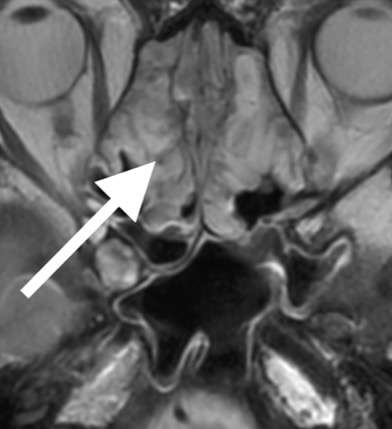

上顎洞炎

33歳女性、元々左上の奥歯に虫歯があり、歯科で治療後も改善しないため受診。頭部MRI検査で左上顎洞に炎症を認めました。したがって、奥歯の感染がすぐ上の上顎洞へ波及した「歯性上顎洞炎」と考えられました。

歯性上顎洞炎